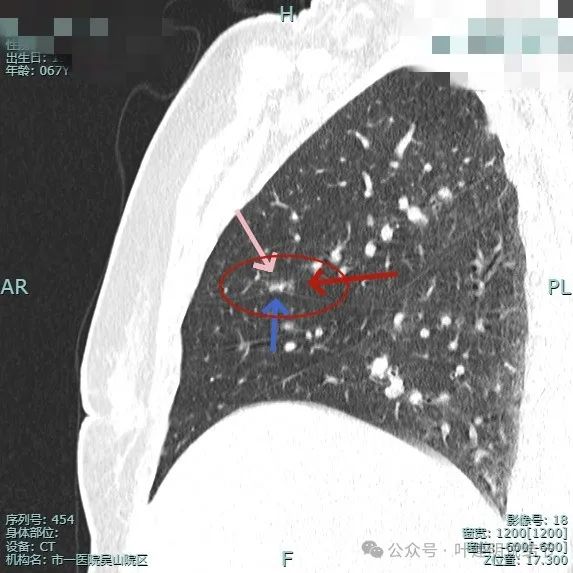

部分边缘毛刺,边缘区域有磨玻璃成分,有微小血管进入,灶内空泡征。

微血管进入病灶,灶内点状高密度。

叶间裂牵拉向病灶侧,此视角看瘤肺边界较为清楚。